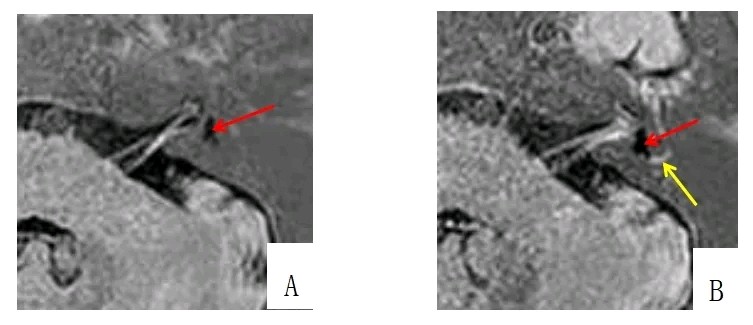

以往,由于该病诊断主要基于患者主观自述、缺少客观性的检查,所以梅尼埃病临床诊断较为困难。目前,认为梅尼埃病的结构基础与内耳淋巴囊扩张密切相关(包括前庭球囊、耳蜗导水管),也称内淋巴积水。此理论获得业内广泛认可,也为该病影像学诊断提供了坚实的理论基础。 常规开展内耳延迟增强检查技术。因为内耳延迟增强MRI可以区分常规内耳MRI不能区分的内淋巴和外淋巴间隙,因此已经成为临床实践中各种内耳疾病患者的首选成像技术。与经鼓膜和咽鼓管注射钆对比剂相比,经静脉注射钆对比剂患者无需麻醉、操作简单,可同时显示双侧内耳,效率更高,而且有效避免了引入外源性对比剂可能造成的副作用。

图片发自160App